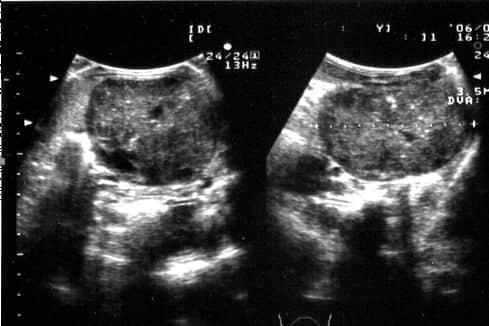

图5、左侧肋弓后方纵向扫查声像图显示左肾(大箭头)与右肾(小箭头)相比,左肾明显增大,左肾被膜光滑,内部的正常结构消失,呈高低相间的混响回声。

图6左侧肋弓后方纵向扫查声像图显示左肾被膜完整光滑,内部的正常结构消失,呈高低相间的混响回声。